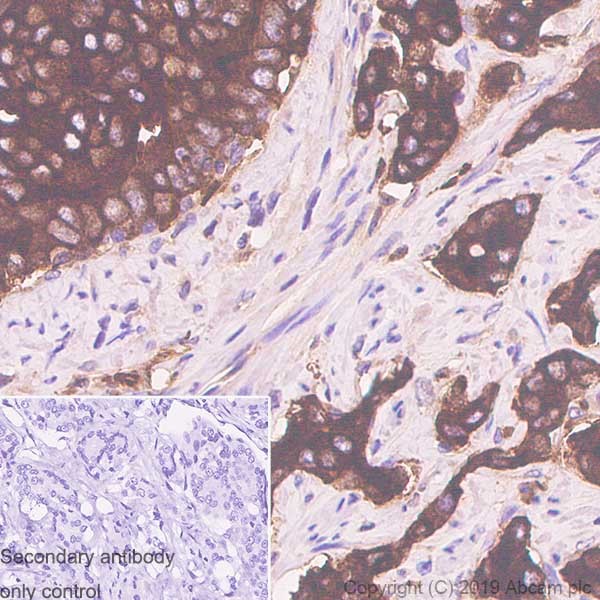

Immunohistochemistry (Formalin/PFA-fixed paraffin-embedded sections) - Anti-PAP antibody [rACPP/1338] (AB238037)

Immunohistochemical analysis Formalin-fixed, paraffin-embedded human Prostate Carcinoma tissue stained for Prostatic Acid Phosphatase using ab238037 at 2 μg/mL (for 30 minutes at RT) (Staining of formalin-fixed tissues requires heating tissue sections in 10mM Tris with 1mM EDTA, pH 9.0, for 45 min at 95°C followed by cooling at RT for 20 minutes).